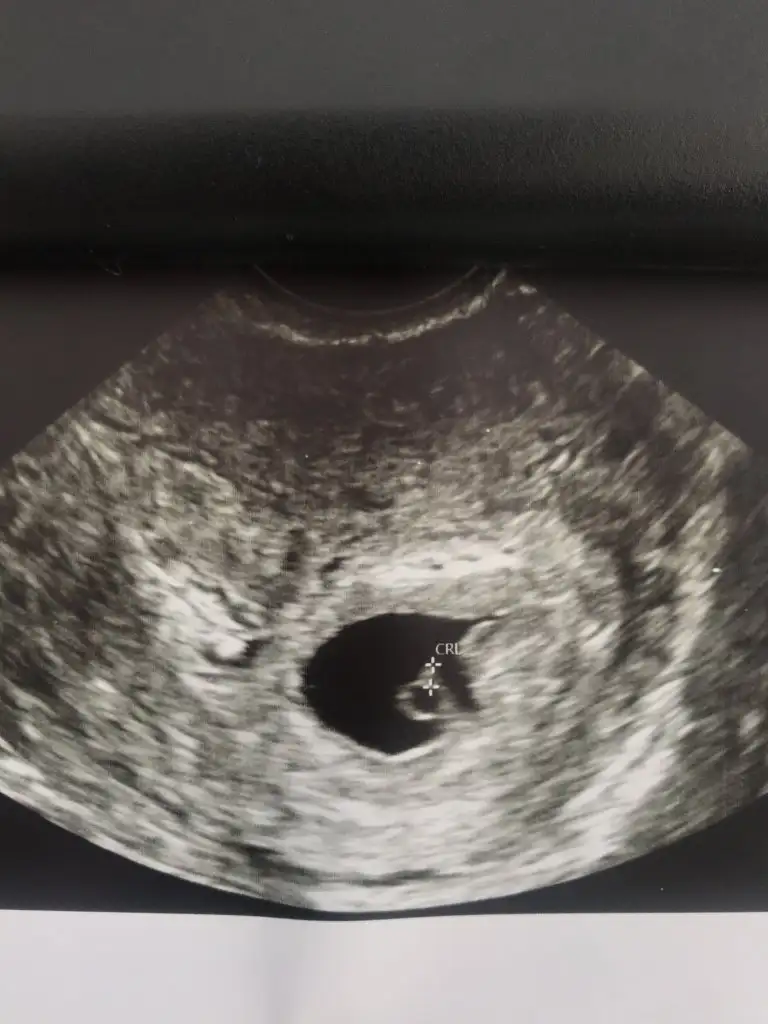

Bugün 7+0 takvime göre. Kese olması gerektiği kadar büyümemiş. Yolk kesesi var altında biraz kanama alanıyla. Bebek ise yok hala.

Progestan iğne yaptılar, ilaç olarak da verdi sabah akşam. Yatak istirahatiyle haftaya salı tekrar kontrol dedi. %10luk ihtimalle o zamana oluşabilirmiş. İlaca rağmen kanama durmayıp düşük de olabilirmiş. Nedense umudum yok her ne kadar Allahtan ümit kesilmese de.